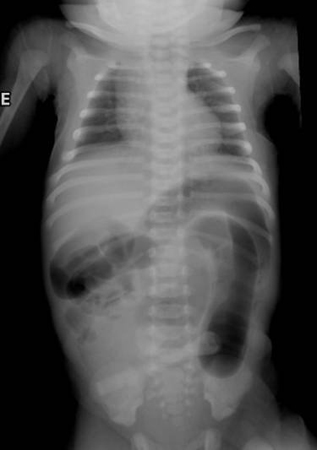

Radiografia abdominal de neonato com padrão fecal anormal e constipação. Os cólons transverso e descendente dilatados são sugestivos de doença de Hirschsprung

Do acervo de Dr. KuoJen Tsao; usado com permissão